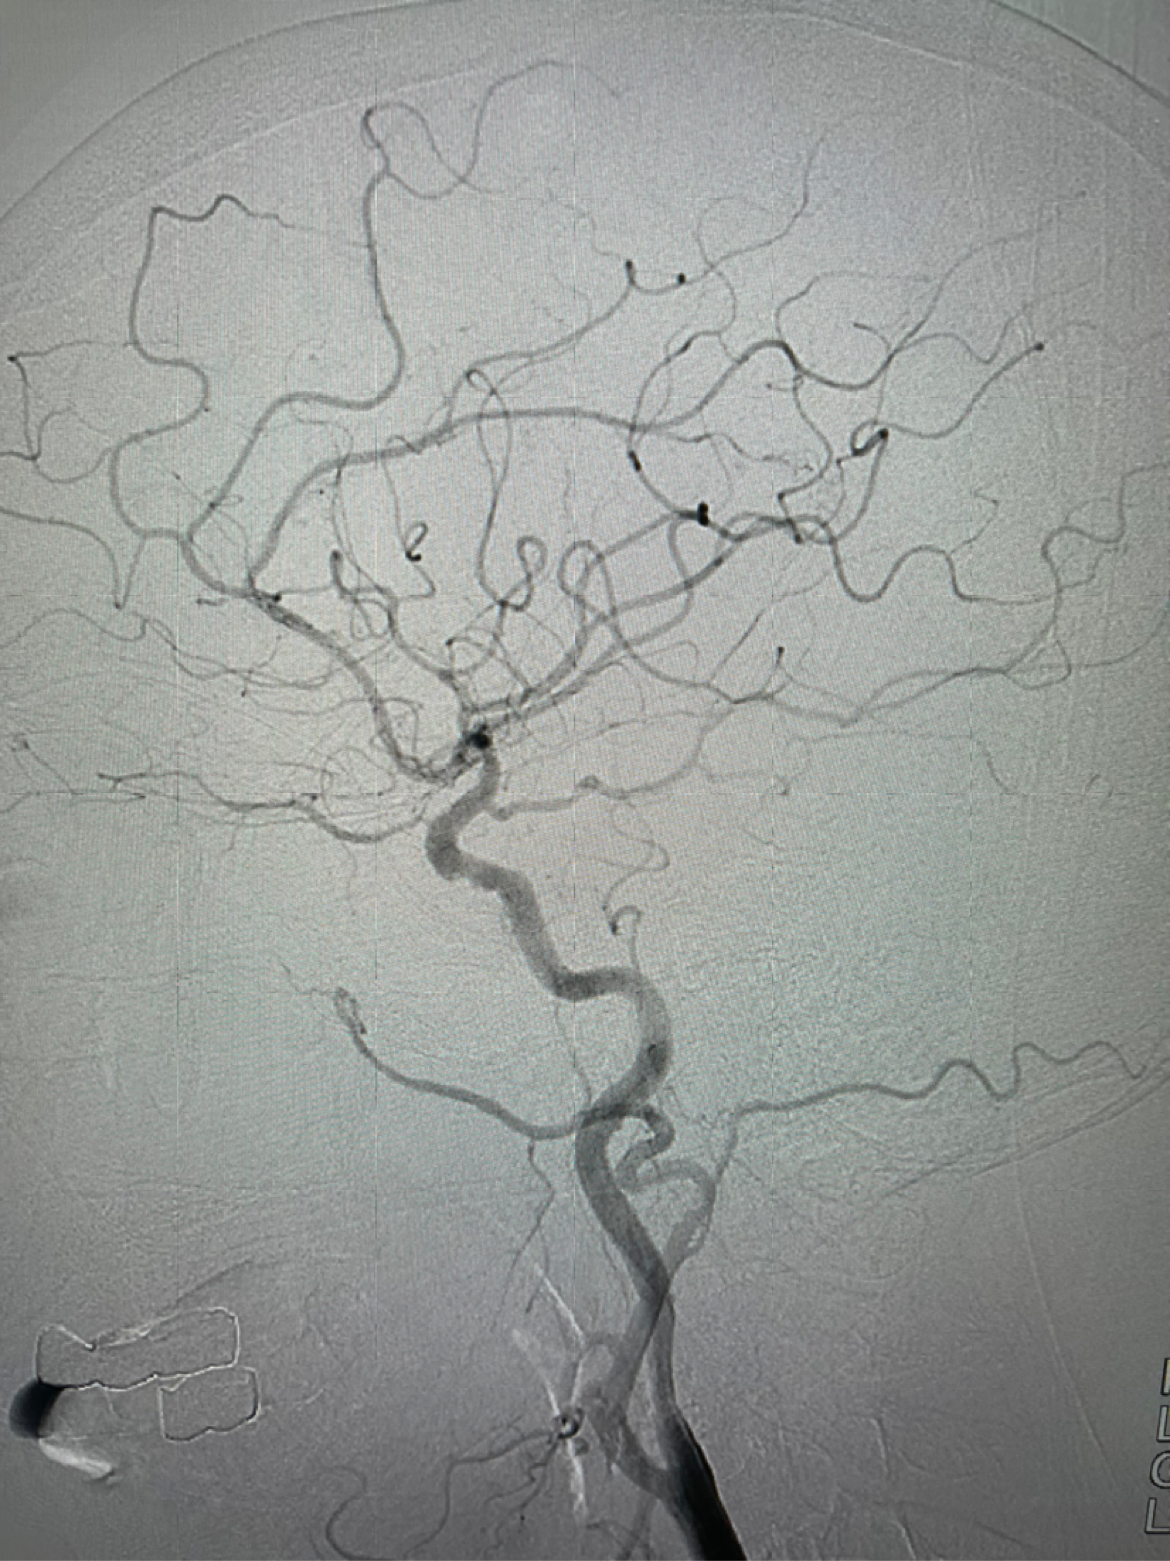

左侧颈内动脉侧位造影